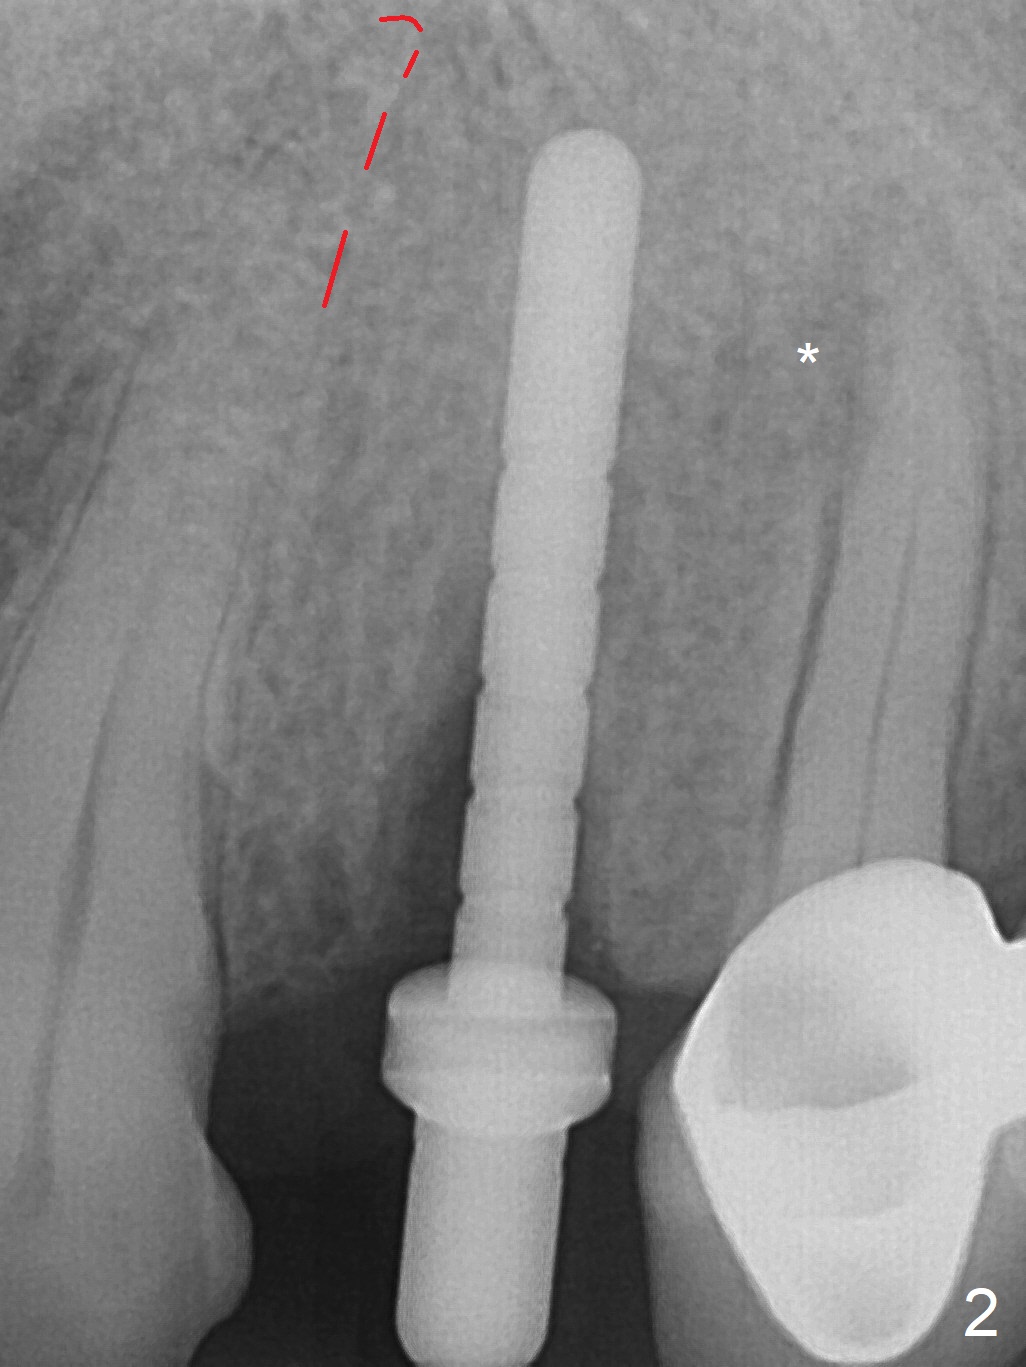

RPD Clearance